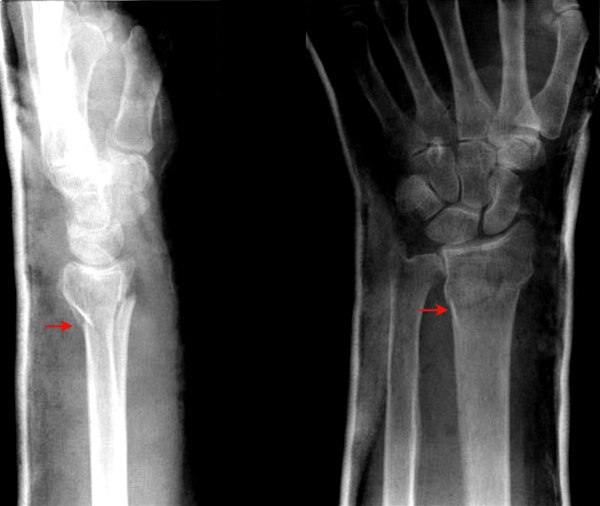

Fraktur ( rød pil) gennem distale radius. Sidebilledet til venstre viser med let dorsalvinkling af distale segment (gaffelformet fejlstilling), og denne frakturtype kaldes også for en Colles fraktur.

Frontalbillede til højre viser at brudlinjen går ind i ledfladen (intra-artikulært), dog uden spring i ledfladen.